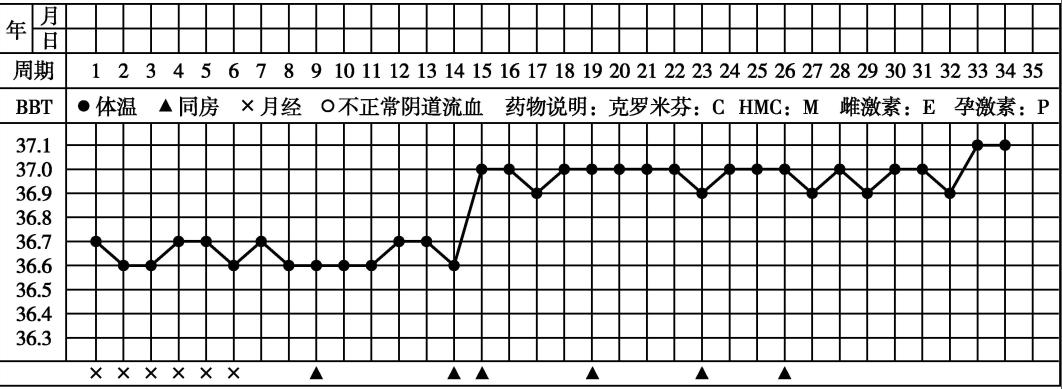

4.基础体温(basal body temperature,BBT)测定 双相型体温的已婚妇女出现高温相18日持续不降,早孕可能性大。高温相持续超过3周,早期妊娠的可能性更大。

早孕期基础体温波动图